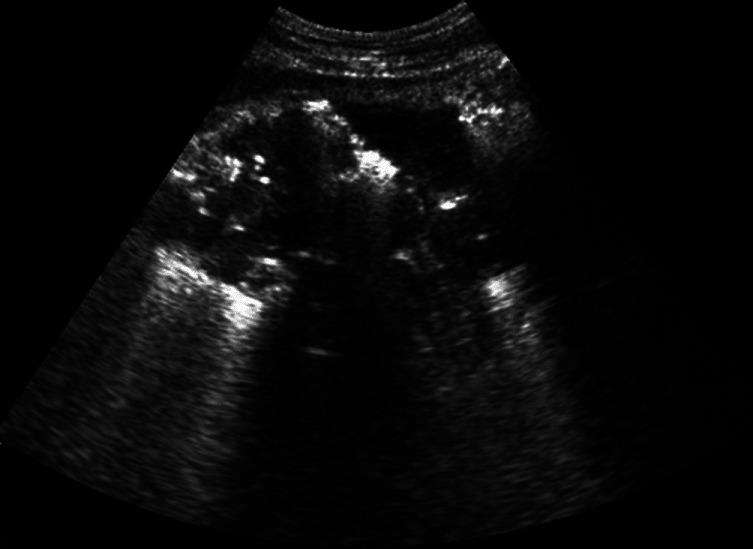

We present our experience of 22 cases of emphysematous pyelonephritis (EPN) treated from 1996 to 2012. Medical records were analyzed retrospectively for demographic profile, presence and duration of diabetes mellitus, and mode of clinical presentation. EPN was diagnosed based on demonstration of intra-renal gas by plain X-ray, ultrasound, and/or computed tomography (CT) scan. Details of medical treatment, reason for surgical intervention, and final outcome were recorded. Univariate analysis was performed to identify risk factors for mortality and P value of less than 0.05 was taken as significant. Twenty-two cases (6 males, 16 females) of EPN were diagnosed. Seven cases presented with acute pyelonephritis, seven cases with urosepsis, and the remaining eight patients with multi-organ dysfunction. CT grading of EPN was class IV in three, class III in four, class II in 14, and class I in one. All were initially managed medically with parenteral antibiotics. Ten patients needed additional surgical intervention. The overall survival rate was 86.3% (19/22). Among the risk factors analyzed higher CT grade, altered sensorium and thrombocytopenia were significantly associated with mortality. We conclude that a more conservative approach in managing EPN has become the standard of care. Patients having high CT grade of lesions (III and IV) with altered sensorium and thrombocytopenia at presentation are more likely to die due to the disease and may be better managed by an aggressive surgical plan.